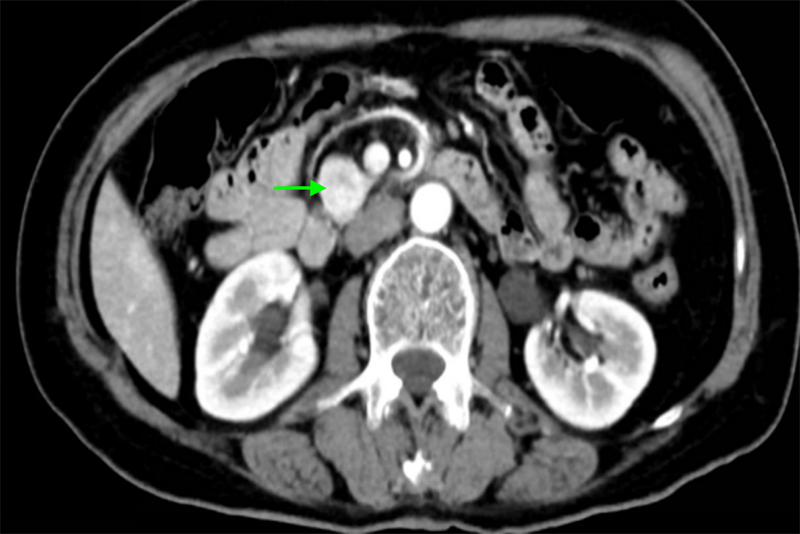

經(jīng)檢查,陳大嬸有低血糖癥狀、代謝性腦病,進(jìn)一步行PET/CT檢查及腹部增強(qiáng)CT檢查后考慮為胰島素瘤。內(nèi)分泌科立即組織肝膽胰外科、神經(jīng)內(nèi)科、內(nèi)分泌科、臨床營(yíng)養(yǎng)科、麻醉科等多學(xué)科聯(lián)合診療,專家們討論后一致認(rèn)為陳大嬸的胰島素瘤有明確手術(shù)指征,于是轉(zhuǎn)入肝膽胰外科進(jìn)一步手術(shù)治療——腹腔鏡探查、胰腺鉤突腫瘤切除術(shù)。

專家團(tuán)隊(duì)進(jìn)行了精心的術(shù)前準(zhǔn)備,并制定了精細(xì)化麻醉方案。術(shù)中,肝膽胰腺外科手術(shù)團(tuán)隊(duì)參考術(shù)前CT資料及術(shù)中腔鏡超聲精確定位腫瘤,將胰島素瘤完整切除,整個(gè)手術(shù)過程時(shí)間僅為80分鐘,出血量?jī)H為5ml。術(shù)后,患者血糖水平恢復(fù)到正常水平,認(rèn)知障礙逐步得到改善,一周后復(fù)查CT未見胰漏。出院前,陳大嬸體力、飲食、精神等方面完全恢復(fù)正常,已能和家人順利交流,終于擺脫了被誤解的慘痛經(jīng)歷。